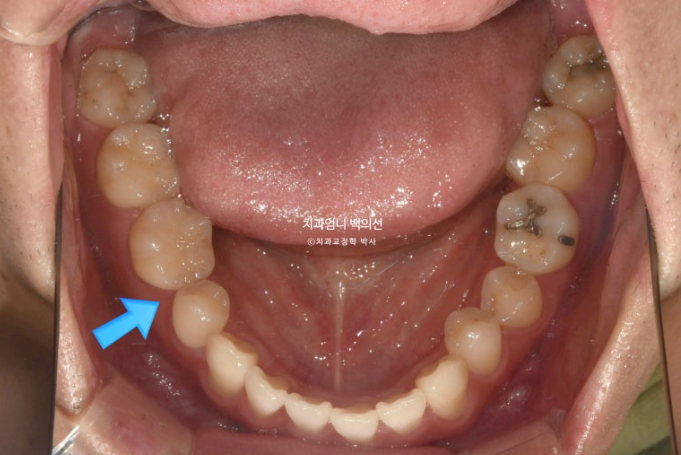

파란화살표 작은어금니와 큰어금니가 반대교합입니다.

흰선 사이 작은어금니 하나가 결손상태이고 결손된 치아 쪽으로 주변 치아들이 쓰러져 있습니다.

파란화살표에 작은어금니 하나가 없습니다.